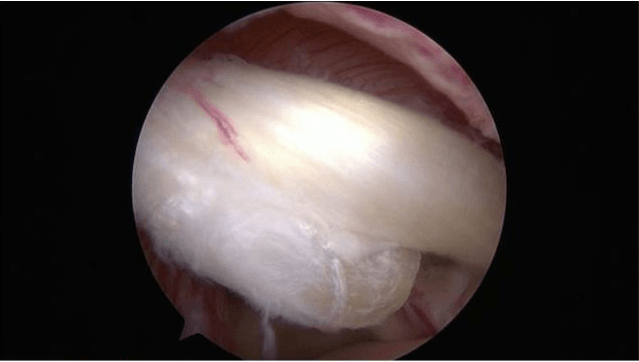

Treatment is essentially surgical and varies depending on the type of injury:

- Well a resection of the damaged umbilical cord

- Bien una reinserción del rodete

It is common to associate these procedures on the labrum with a tenotomy or tenodesis of the long biceps tendon (cutting and fixation of the tendon).